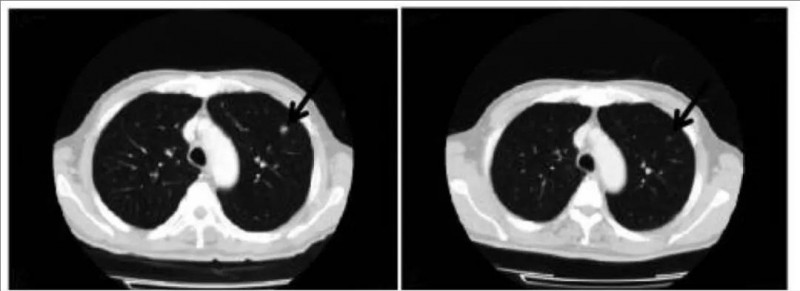

令人鼓舞的是,表现出完全缓解(CR)的患者TR05,其转移性病变在γδT细胞治疗7个月内消失,且至今(治疗完成后超过36个月)仍保持无癌生存。下图展示了该患者(TR05)在治疗开始时和治疗3个月后,转移性病变的代表性CT图像,正是在这3个月的间隔内,两个病变在宏观上消失了(详见下图)。

▼该患者γδT细胞治疗前后转移性肺肿瘤的CT图像对比

▲图源“Cancer Immunol Immunother”,版权归原作者所有,如无意中侵犯了知识产权,请联系我们删除

注:治疗前,通过CT成像可观察到5个转移性肺病灶;此处描绘的一个转移部位在治疗开始后-3个月、0个月、3个月的变化,测量结果分别为1.26×1.08cm(未显示)、1.33×0.97cm(左)、0.00×0.00cm(右)。